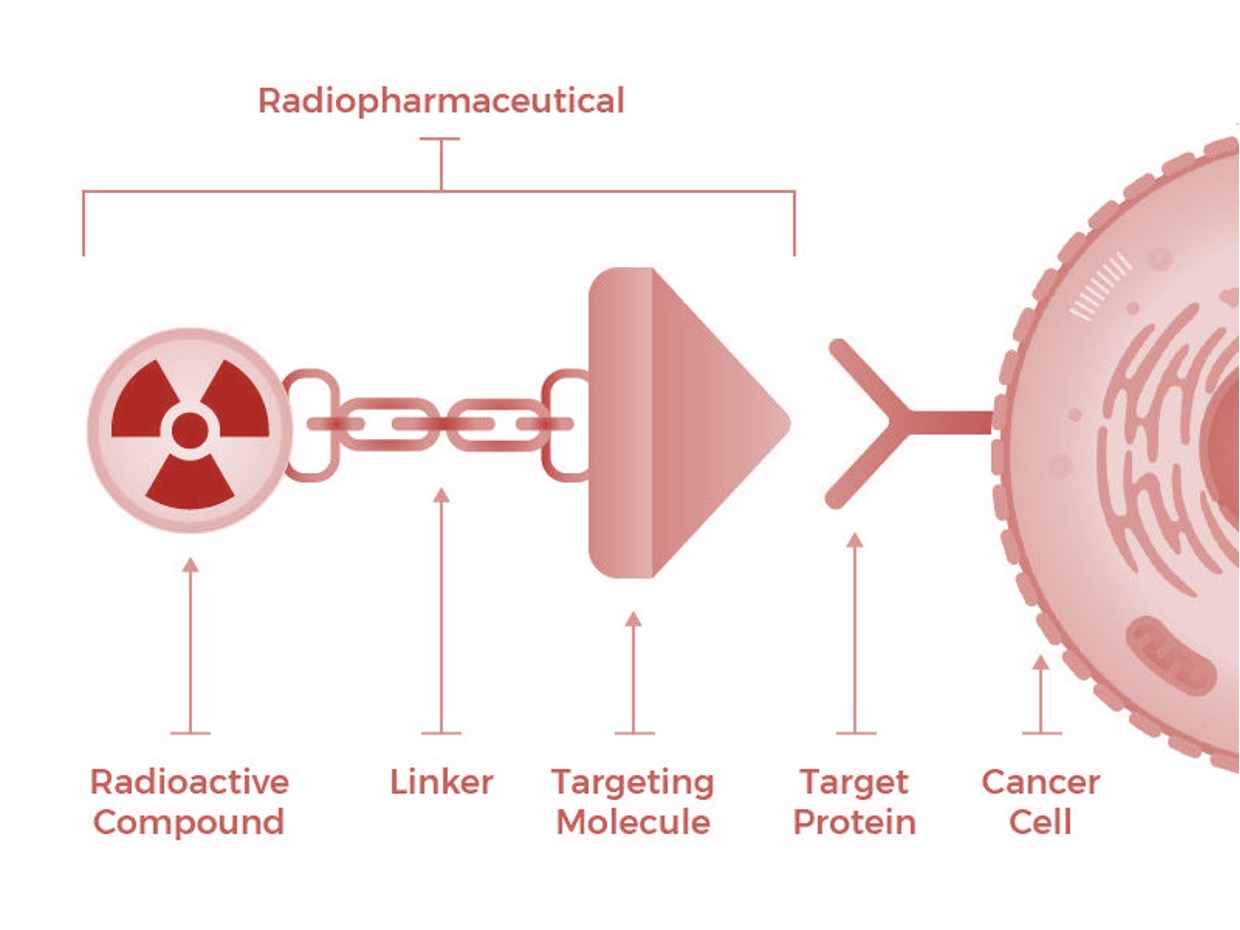

Increasingly, pharmaceutical makers are developing new drugs (radiopharmaceuticals) capable of delivering the cancer-killing power of radioisotopes directly to tumors while leaving the surrounding healthy tissue intact. Like a puzzle piece, these drugs attach only one way – directly to the proteins associated with the cancer – for maximum efficiency.

Diagram: Radiotherapeutics target and eliminate cancer cells with precision. Adapted from National Cancer Institute.